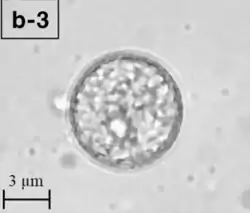

Balamuthia mandrillaris es una ameba heterótrofa de vida libre, que consta de un complemento estándar de orgánulos rodeados por una de tres capas de la pared celular , y con un anormalmente grande, vesicular núcleo . En promedio, un Balamuthia trofozoito es de aproximadamente 10 - 16 micrómetros de diámetro. Los quistes caen aproximadamente en este rango también (6-30 μg).